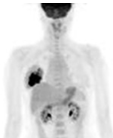

PET scan. Εμφανής η υπερμεταβολική εστία στον δεξιό μαστό (Ευγενική παραχώρηση Dr. V. Penopoulos)